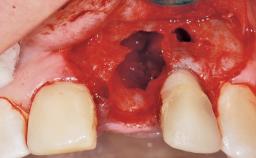

Immediate Flapless Placement of an Implant in a Maxillary Left Central Incisor Site

A 42-year-old female patient was referred to our clinic at the School of Dentistry of the University of São Paulo in November 2004, presenting a deficient restoration in the upper left central incisor. The clinical examination revealed no gingival retraction or any signs of gingival inflammation and, therefore, previous periodontal treatment was not considered. The patient presented a high lip line at full smile and a thin tissue biotype. This combination characterized a high-risk situation from an anatomic point of view, which required careful preoperative planning and cautious surgical execution.